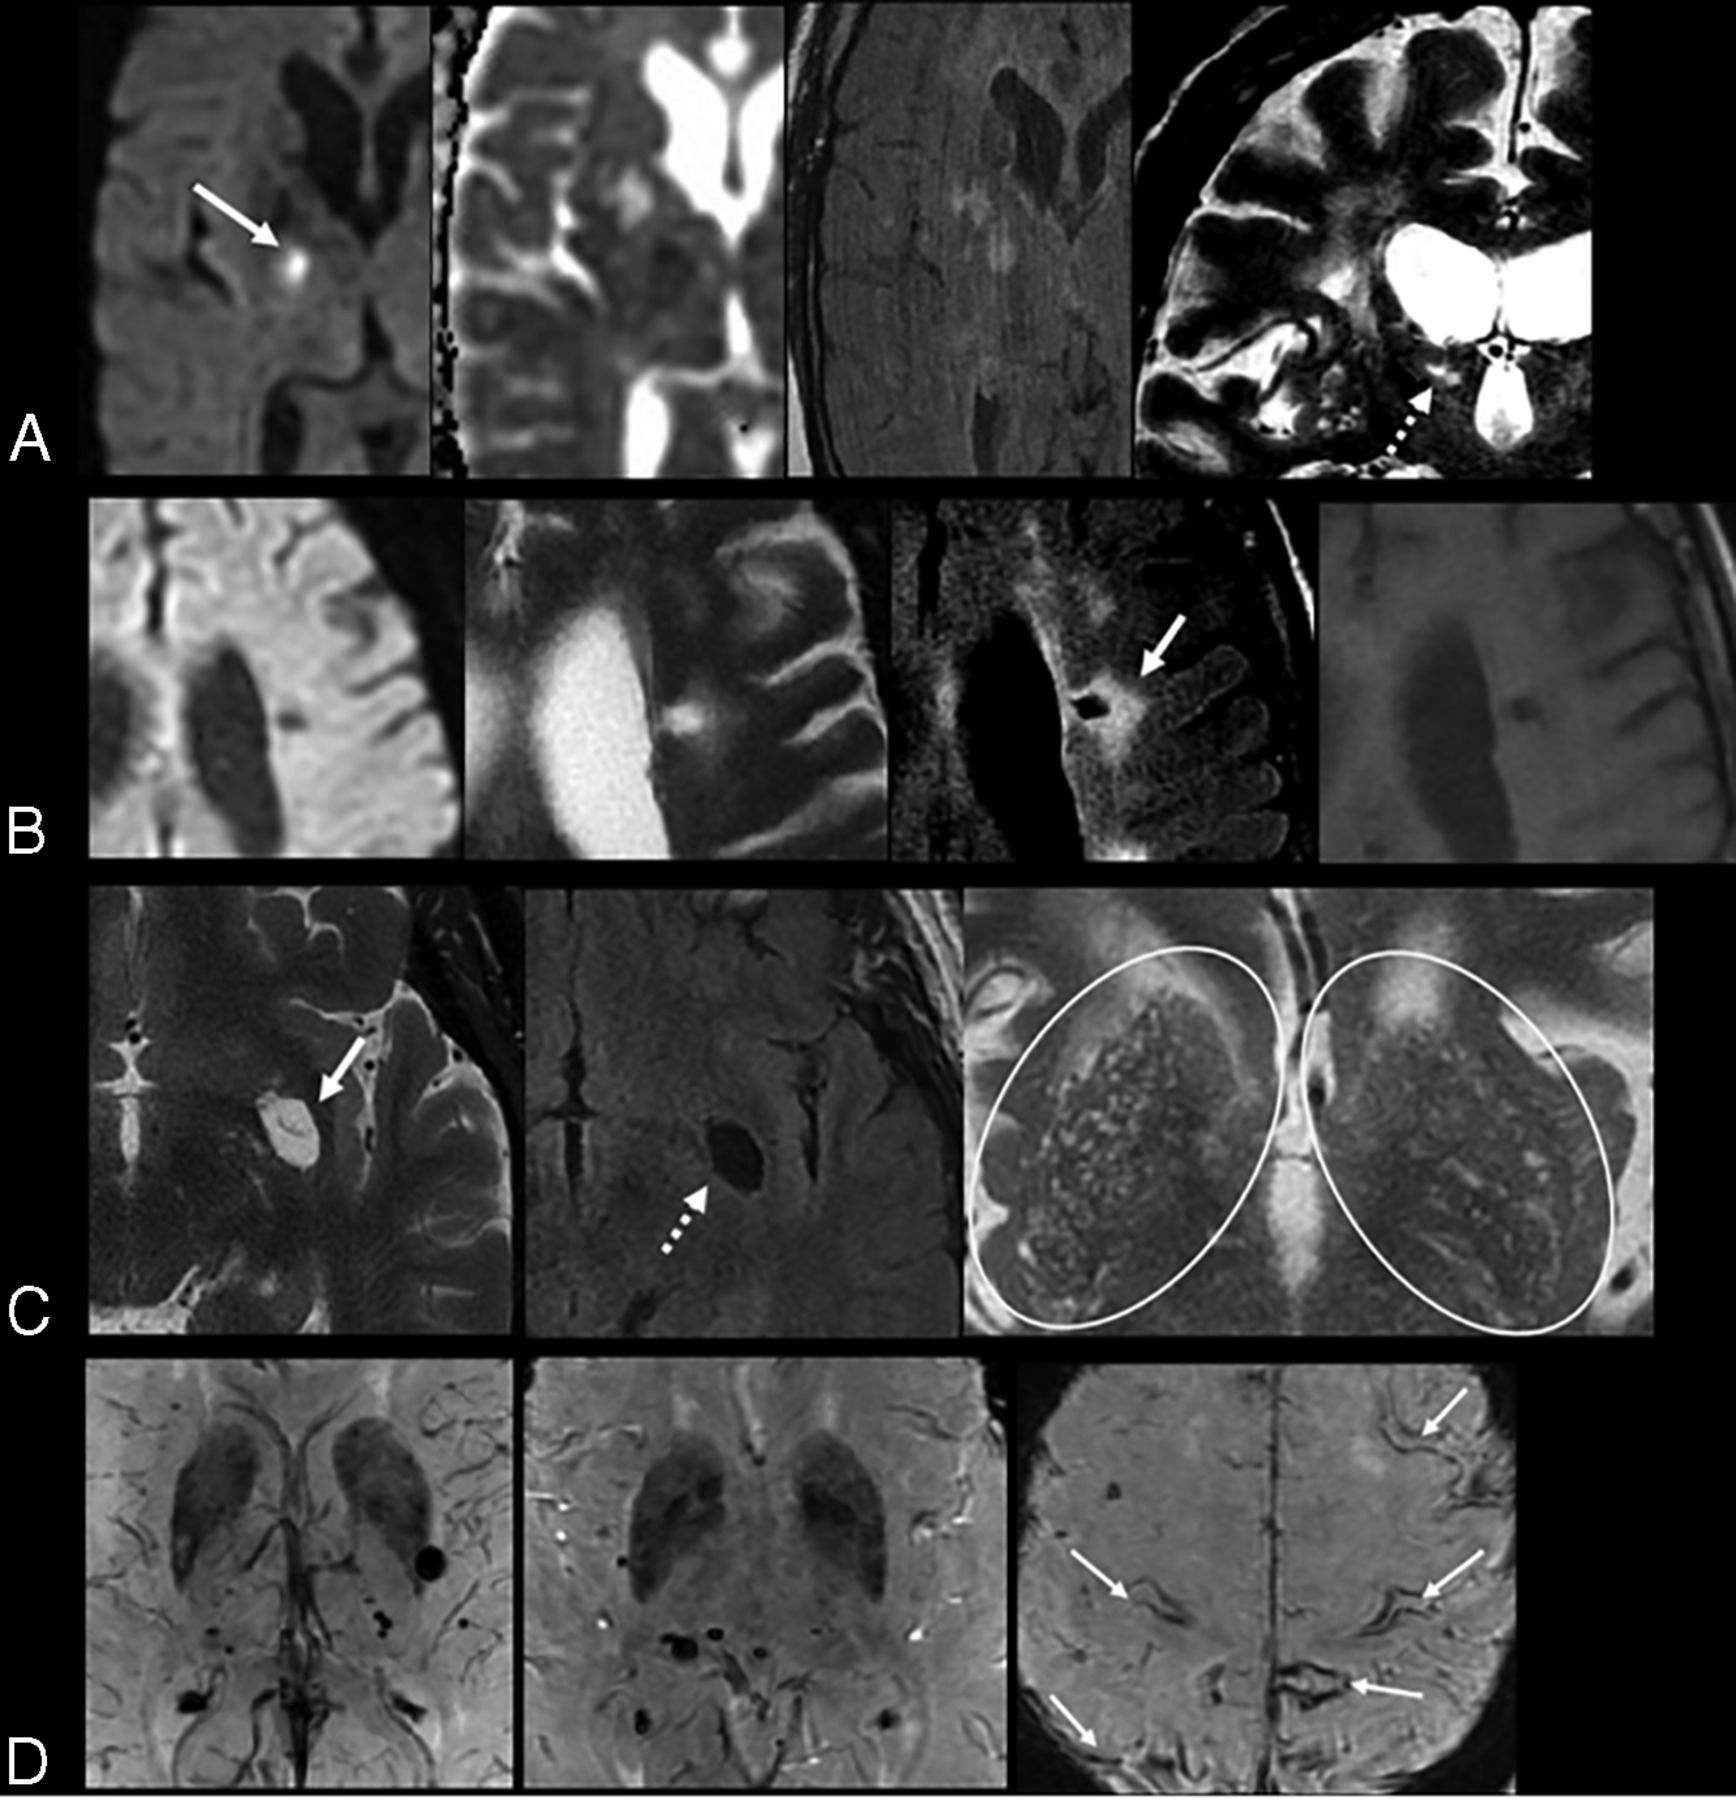

Total SVD Score

Although the neuroimaging markers have typical characteristics, in practice, it is difficult to distinguish lacunes, PVS, and WMH of presumed vascular origin because they are often closely related. A few studies have suggested combining these MR imaging markers and using a more comprehensive approach to assess total SVD burden.33,40 Total SVD score is a simple and pragmatic way of assessing overall brain health and has been shown to be a prognostic indicator of cognitive decline and recurrent stroke (Fig 5). The total burden of lesions in specific anatomic locations can also be used for lesion-symptom associations and has been shown to be associated with cognitive impairment and gait and mood disorders.5,40,41 For instance, a total SVD score in CAA was proposed by Charidimou et al33 and can potentially provide a more practical framework to better evaluate the effect of CAA-related brain damage on clinical outcomes. A similar total MR imaging SVD burden approach was proposed in HA by Klarenbeek et al.42 The imaging rating points of total SVD burden are outlined in Table 2.

High SVD burden in a 55-year-old man with a history of arterial hypertension. Note multiple microbleeds in the left thalamus and occipital lobe (dotted arrows) on SWI (A), remote lacunar infarcts in the right centrum semiovale (white arrows, B), and WMH Fazekas 2 on FLAIR (B). More than 20 dilated perivascular spaces are seen on axial T2WI (circle, C) and remote lacunar infarct in right lentiform nucleus (white arrow, C). The total SVD score is 4. The patient developed an acute lacunar infarct (black arrow) on DWI (D) 10 months later.

Imaging in HA versus CAA

HA (type 1) and CAA (type 2) are the most common sporadic SVD types in older adults (Fig 4 and Table 2) with intrinsically different pathophysiology, clinical significance, and prognosis.15 HA predominantly affects small perforating end arteries of the deep gray nuclei and deep white matter, whereas CAA results from β-amyloid deposition within the cortical and leptomeningeal arteries. Both types are common causes of ischemic manifestation, intracranial hemorrhage, and cognitive impairment. Although both types can be associated with similar imaging markers, including CMB, WMH, lacunar infarcts, and PVS, the anatomic distribution of these markers can be helpful to differentiate these 2 entities radiologically. Lobar/superficial and cortical distribution is consistently associated with CAA, whereas the involvement of deep brain regions and the basal ganglia is most often associated with HA (Fig 4 and Table 2).15,33,36,42⇓-44 Furthermore, deep CMB are typically associated with arteriolosclerosis, whereas a strictly superficial/lobar location is characteristic of CAA.10 CAA is characteristically associated with lobar CMV, cSS, centrum semiovale perivascular spaces, and multiple punctate FLAIR WMH (typically >10) with a predilection for the posterior regions.15,33,44 A peri-basal ganglia pattern of WMH is strongly linked to arteriolosclerosis (Fig 4).15